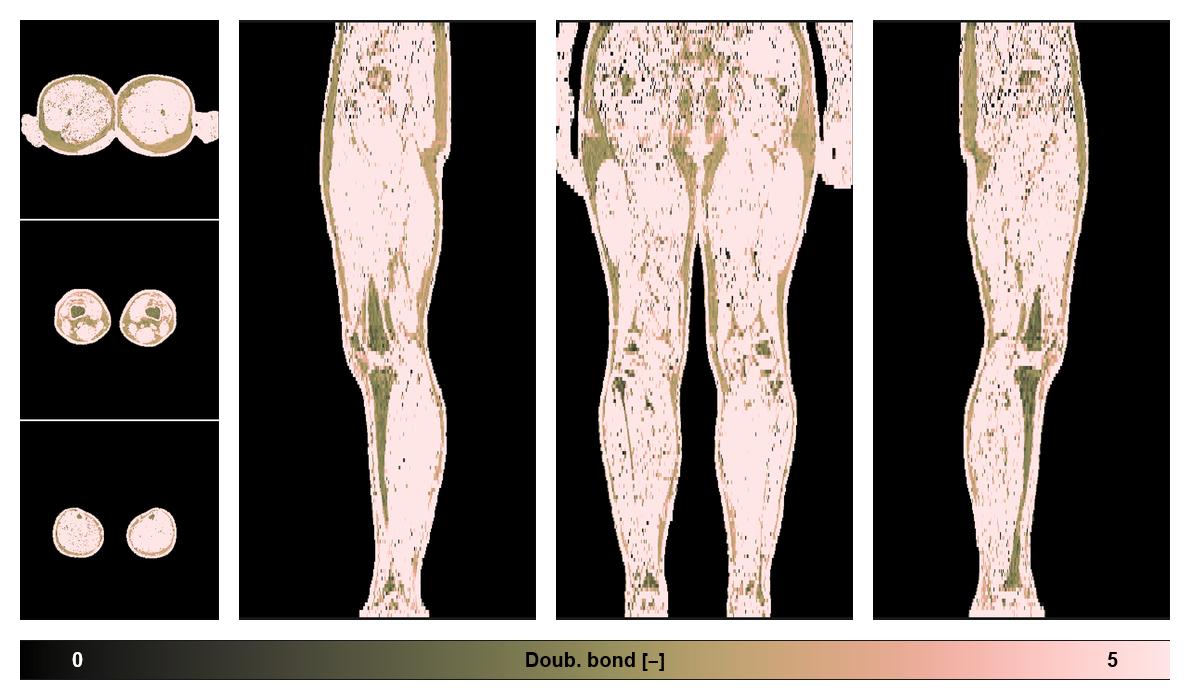

• Number of double bonds in subcutanious fat

Number of double bonds in subcutanious fat.